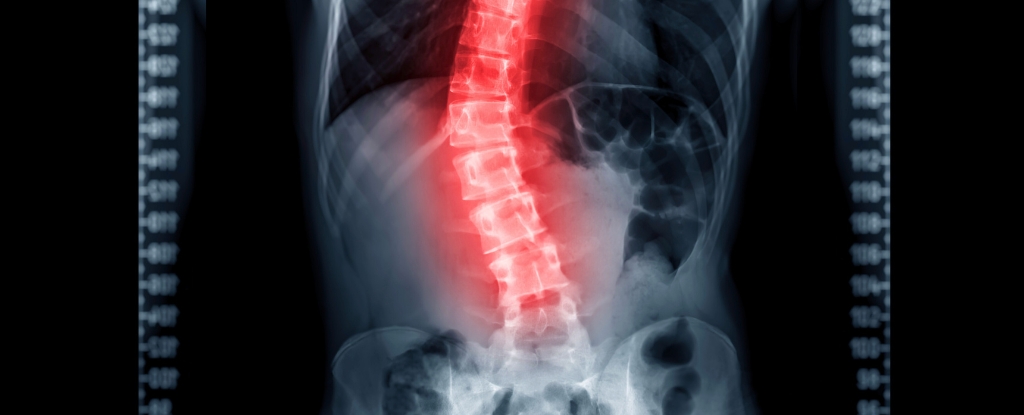

Back Pain Impacts 60% of Us - Here's How Your Curvy Spine Might Cause It Science Alert - September 4, 2025

Your spine is composed of 33 bones known as vertebrae, which are stacked one on top of the other. The resulting column is divided into five segments: cervical (in the neck), thoracic (at the same level as the chest), lumbar (at the level of the abdomen) and sacral (connecting with the pelvis). The fifth, the coccyx, is located at the very bottom of the spine (the tailbone) - and is very painful when injured.